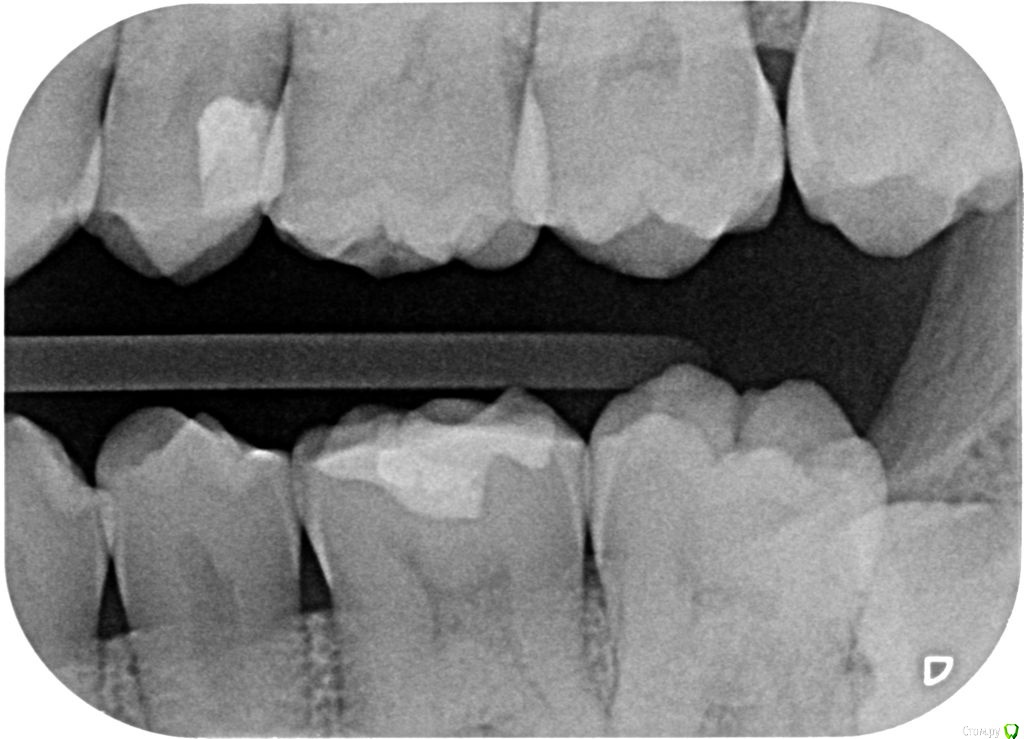

janis1 Опубликовано 14 декабря, 2015 Автор Поделиться Опубликовано 14 декабря, 2015 Итак, продолжение моей эпопеи.Удалось попасть к челюстно-лицевому хирургу-онкологу раньше чем было запланировано. После очного осмотра и изучения КТ, профессор выдал заключение, что никаких проблем по его части он не нашел.После этого я был у терапевта, по поводу 25 -26 зубов, ничего кроме зубного камня на 26 зубе (кстати напомню я недавно делал гигиену ) он так-же ничего не нашел.На всякий случай сделали рентген зубов, даже как я понял с двух сторон, вот снимки: Ну и самое главное - проблема осталась, то-есть уже более двух месяцев я живу с болью в районе верхней челюсти...Что делать дальше не знаю...Очень надеюсь на вашу помощь! Ссылка на комментарий